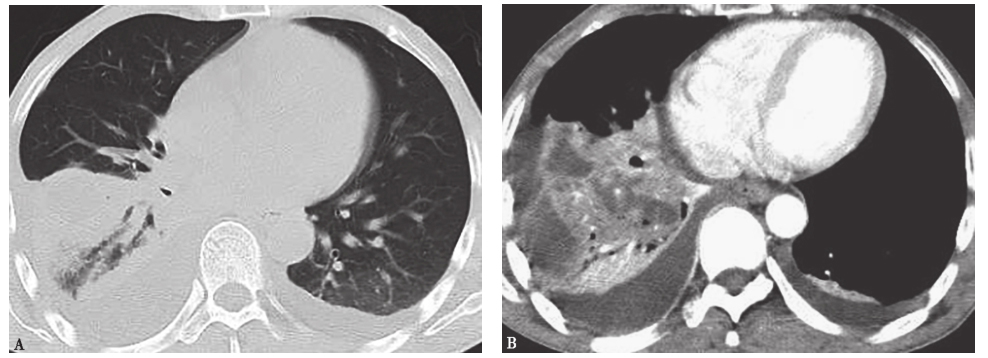

胸部增强CT:右肺下叶实变伴远端肺阻塞性改变,右肺上叶结节,右肺门及纵隔淋巴结肿大,右侧胸腔积液。对比病程初期,右下叶实变伴肺膨胀不全,胸腔积液较前增多(图2)。

图2 入院后第5天胸部CT表现